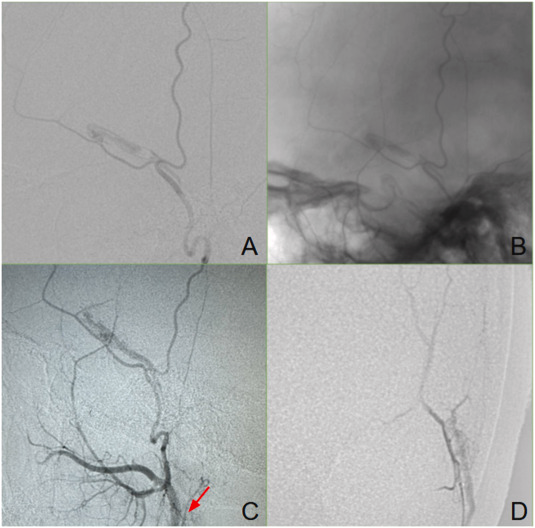

2) Temporal Artery Embolisation – An Advanced Vascular Approach

Temporal Artery Embolisation is an emerging minimally invasive procedure aimed at improving hair loss in selected patients.

This treatment is typically considered in carefully selected cases after proper vascular and clinical evaluation.